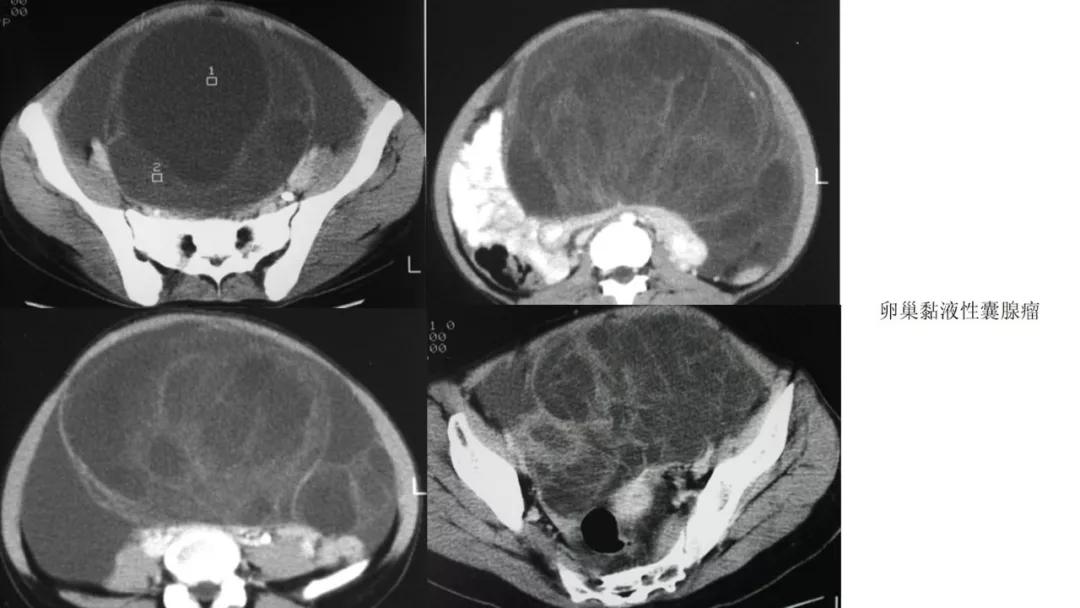

- 卵巢的黏液性肿瘤破裂,上皮和黏液会种植在腹膜引起胶冻样的腹膜假黏液瘤,这一点跟阑尾的黏液性肿瘤类似,都是腹膜假黏液瘤的病因。